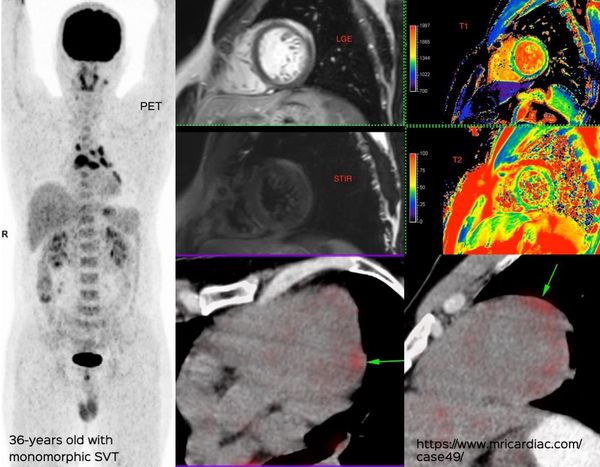

Granulomatous Cardiomyopathy

Combined CMR and PET/CT give synergistic information in patients with granulomatous cardiomyopathy